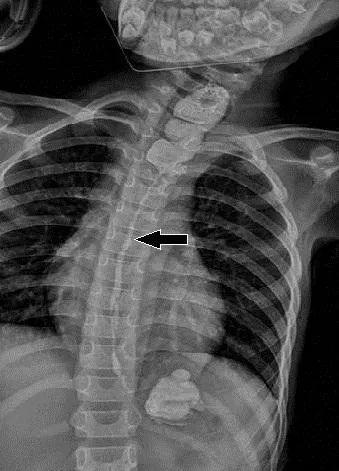

其实孩子喝下的一小口水是空调清洁剂 , 具有很强的腐蚀性 , 一丢丢就能够破坏我们的皮肤 。 这个孩子的食管腐蚀 , 中下段2/3的地方严重狭窄 , 无法使用 , 基本处于报废状态 。 孩子的父母不断责怪自己 , 是他们的粗心才导致了悲剧的发生 。还好医生的医术高明 , 减下一小部分胃代替了孩子报废的食管 , 让孩子恢复了进食能力 , 身体逐渐变得健康 。 看到孩子的身体一天天的好起来 , 父母虽然很欣慰 , 但也有一些后怕 , 对待孩子的安全问题再也不敢掉以轻心了 ,